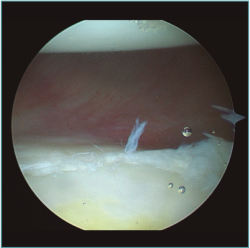

Al realizar la anamnesis, prestamos especial atención a estos síntomas ya que estos episodios repetidos de subluxaciones o microinestabilidad pueden conllevar a lesiones muy complejas e irreparables de la cápsula o, sobre todo, en el cartílago glenoideo (Figura 2).

Figura 2. Visión desde portal posterior del hombro derecho. Se observa una lesión intrasustancia de la cápsula anterior.

Las inestabilidades de hombro que se manifiestan con dolor o subluxaciones son tan incapacitantes como las luxaciones propiamente dichas y en la gran mayoría de los casos requieren resolución quirúrgica(10,11). Hemos visto en varias ocasiones jugadores con cuadros de subluxaciones o microinestabilidad en situaciones de contacto que modifican su técnica de tackle para disminuir la incidencia de estos episodios y de esta forma continuar jugando. Lamentablemente, además de una indefectible disminución de su rendimiento deportivo, estos jugadores a la hora de operarse presentan lesiones capsulares de difícil solución y lesiones condrales precoces.